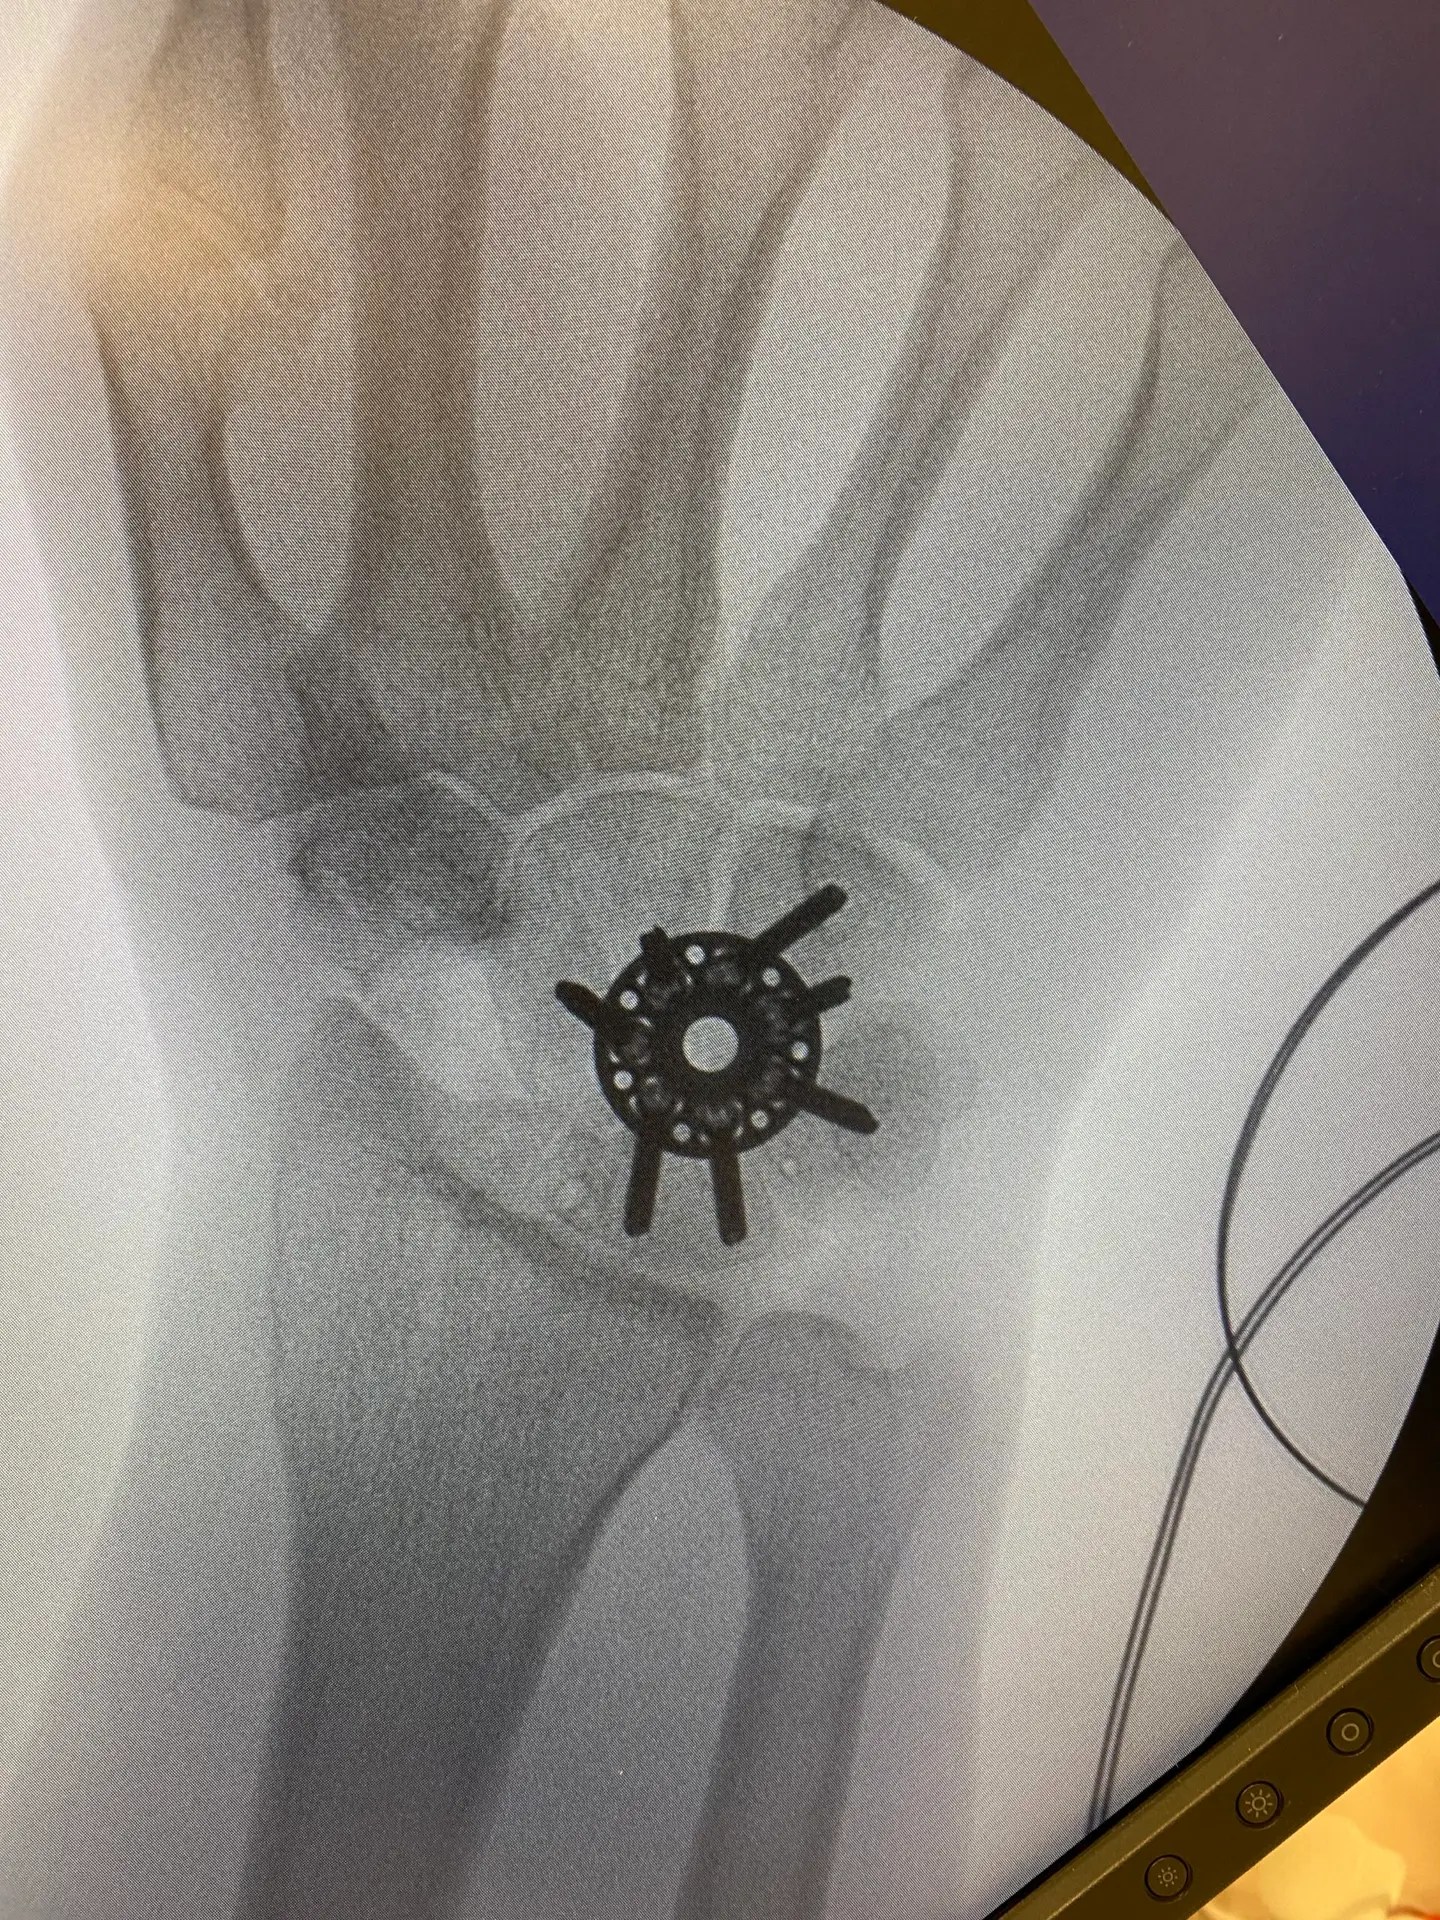

Xray of hand and wrist illustrating hand surgery procedures

Hand and Wrist Surgery

Protecting and improving hand function is another one of James’ passions. The list of conditions affecting the hand and wrist is extensive: common conditions treated at James’ rooms include carpal tunnel syndrome, small joint- and wrist arthritis, Dupuytrens contracture, acute fractures and post-traumatic conditions, tendon injuries, wrist pain and degenerative hand pathologies.

Treatments offered vary from injections and minimally invasive techniques for minor ailments in the consulting rooms, to specialised surgical procedures in the operating theatre. Most hand- and wrist surgeries are performed as day-stay surgery, many of which can be done under local anaesthetic.

• Arthroscopic/keyhole procedures

• Joint replacement surgery